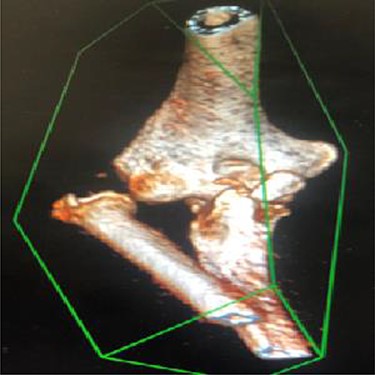

As emergency treatment, we realized a closed reduction of the elbow dislocation under general anaesthesia with X-ray control, the limb was stabilized in a posterior brachiopalmar splint. A computed tomography (CT) confirmed the stage 2 coronoid process fracture and a partial radial head fracture, the PRUJ dislocation was also demonstrated (Fig. 2). The DRUJ and PRUJ dislocations were suggestive of a complete disruption of the interosseous membrane. We managed a surgical treatment the second day of admission. A Kaplan approach was used to reduce the PRUJ dislocation, the annulate ligament was repaired and the radial head fracture was evaluated, as the detached fragment was <20% of the radial head circumference, no fixation was necessary. The lateral collateral ligament (LCL) and the common extensor muscle were repaired. The elbow testing objected a stable elbow from −30° of extension to complete flexion. According to that elbow stability status and the coronoid fracture stage, we decided a conservative treatment for the anteromedial coronoid fracture. Closed reduction of the DRUJ was achieved but it was instable, a fixation with a TightRope was used (Fig. 3). The stability was rechecked and upgrade of the stable range of motion (ROM) was assessed, the elbow was now stable from −20° extension to complete flexion. A sling was used for comfort for 2 weeks postoperatively with physiotherapy and ROM exercises initiated early.

3D reconstruction CT scan of the elbow shows a radioulnar proximal dislocation with O’Driscoll type 2-2 anteromedial fracture.